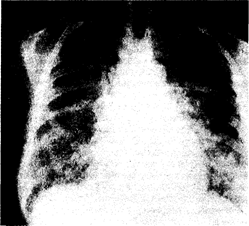

Физикальное обследование обычно малоинформативно; лишь в редких случаях удается выслушать незвучную инспираторную крепитацию. В этот период на рентгенограммах органов грудной клетки легкие представляются интактными либо визуализируется незначительная интерстициальная инфильтрация. По мере прогрессирования патологического процесса явления дыхательной недостаточности нарастают (возрастает частота дыханий, появляется диффузный цианоз кожных покровов). Над всеми легочными полями выслушивается звучная крепитация, дыхание становится шумным, клокочущим; на рентгенограмме органов грудной клетки отмечают распространенную многофокусную альвеолярную и интерстициальную инфильтрацию (рис. 216-1).

Рис. 216-1. Рентгенограмма органов грудной клетки (прямая проекция) больного с респираторным дистресс-синдромом взрослых, развившимся на почве вирусной пневмонии тяжелого течения.

Подобные рентгенологические изменения типичны для всех заболеваний и патологических состояний, указанных в табл. 216-1, и клинически сопровождаются явлениями острой дыхательной недостаточности. Сходная скиалогическая картина наблюдается при развитии отека легких на почве левожелудочковой недостаточности (гл. 26). Внезапное развитие РДСВ вынуждает ограничиваться рентгенографией органов грудной клетки в положении лежа; кроме того, ввиду тяжести состояния больные не в состоянии осуществить полноценный вдох и задержку дыхания. При этом на рентгенограмме нередко визуализируется кажущееся расширение сердечно-сосудистой тени, что иногда порождает гипердиагностику кардиогенного отека легких.